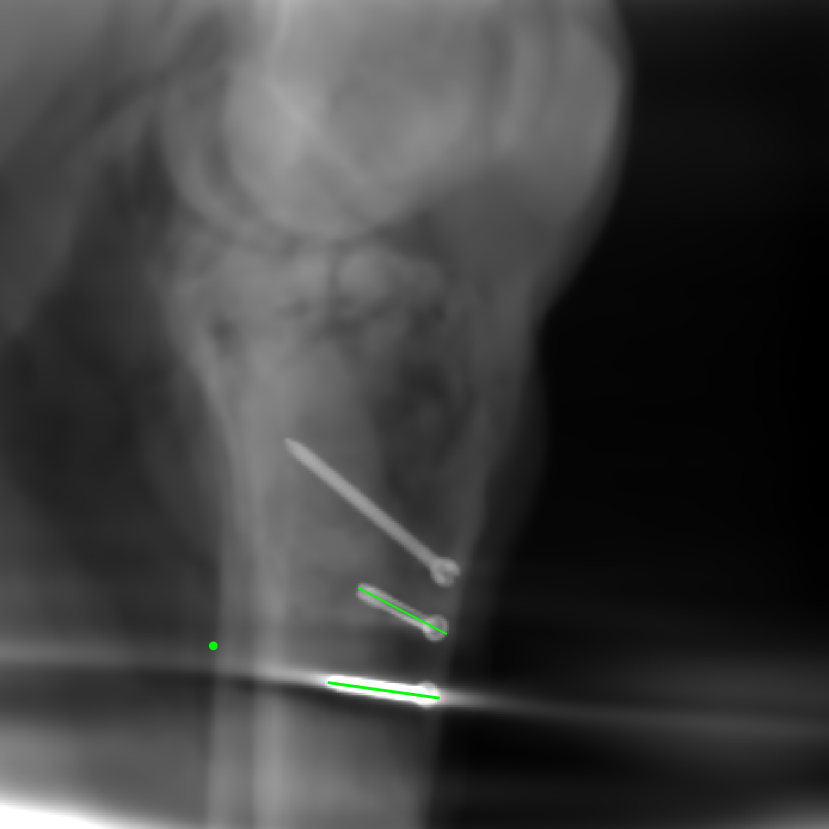

5.4 Real Knee Data with Metal Implants

Refer to caption

Figure 13: Three examples of synthetic perspective projection images for training, intensity window: [0, 4]. The appearance (e.g., image contrast and metal image resolution) of such DRR training images is different from that of real projection images in Fig. 14.

0superscript00^{\circ} perspective

[Uncaptioned image]

(a) 32.56, 109.85

(b) 18.91, 19.54

180superscript180180^{\circ} perspective

(c) 28.11, 112.16

(d) 15.80, 19.27

View difference

0superscript00^{\circ} and 180superscript180180^{\circ} RGB

DRR reference

(e) 29.72, 111.80

(f) 17.14, 19.38

Pix2pixGAN

(g) 29.72, 111.80

(h) 17.50, 19.70

(Fig. 14 continues in the next column.)

TransU-Net

(i) 29.72, 111.80

(j) 16.23, 19.25

Figure 14: The results for the real cadaver leg data. The green dots mark the positions of landmarks in the corresponding reference images. In the first column, the arrows indicate the bone cavity/fracture structures. In the second column, the solid lines mark the widths and heights of the metals. The green ones are measured from the DRR reference, while the red ones are measured in the corresponding perspective projection image. In the last column, the lines mark the centerlines of the metal screws, where the green lines are those from the reference image. The lengths of the lines in mm are displayed in their corresponding subcaptions. Intensity window: [0, 4]. Please zoom in for better visualization.

The complementary view setting for learning perspective deformation is also evaluated on real CBCT projection data. In this evaluation, real CBCT projection data from a dataset of knees with metal implants is used for testing, while DRRs created from volumetric CT datasets with inserted metals is used for training. Three exemplary DRR perspective projection images for training are displayed in Fig. 13, in which synthetic metal implants are inserted [34]. The appearance, e.g., image contrast and metal image resolution, of such DRR training images is different from that of real projection images in Fig. 14. In Fig. 14, the results for three knees, with and without metal implants, are displayed. The first and second rows are the 0superscript00^{\circ} and 180superscript180180^{\circ} perspective projections, respectively, rebinned to the virtual detector with geometric calibration based on their respective principal points and projections of the world origin. The third row displays their difference images, where the magnitude of deviation increases from the center towards the outside like it does in DRRs with an ideal scan trajectory (e.g., Fig. 6(e)), although real projection data suffer from various physical effects like beam hardening and Poisson noise. The fourth row displays the RGB stacks of 0superscript00^{\circ} and 180superscript180180^{\circ} perspective projection images. The magenta and green regions indicate structures with considerable perspective deformation, for example, the knee patella in Fig. 5.4, the top parts of the two metals in Fig. 5.4, and the bottom two screws in Fig. 5.4. The fifth row displays reference images, which are orthogonal projections of iterative reconstruction volumes from measured CBCT projection data. In the reference images, a total of five landmarks are selected, with the positions being marked by the green dots: In Fig. 5.4, two positions at the edges of the knee patella are marked; In Fig. 14(e) and Fig. 14(f), one position at the left edge of the fibula is marked for each image. In addition, a rectangular frame for the two metals is marked by the green dashed lines, while its width and height are indicated by the green solid lines, which are 29.71 mm and 111.99 mm, respectively. In Fig. 14(f), the centerlines of the bottom two screws are sketched by the green lines, which have the lengths of 17.14 mm (middle screw) and 19.38 mm (bottom screw). The corresponding rectangular frame for the two metals and the screw centerlines in the perspective projection images are marked as well, but in red color. In Fig. 14(a), the width and height of the metals are 32.56 mm and 109.85 mm, which have deviations of 2.84 mm and -1.95 mm to the reference ones, respectively. In Fig. 14(b), the centerline lengths are 18.91 mm and 19.54 mm, which have deviations of 1.77 mm and 0.16 mm, respectively. Although the bottom screw has little length deviation to the reference, the orientations of both screws are obviously deviated. The sixth row shows the results of Pix2pixGAN using 0superscript00^{\circ} and 180superscript180180^{\circ} polar inputs. For all of the landmarks, the green reference dots are all located accurately in the Pix2pixGAN images. The rectangular reference frame also accurately covers the metals in Fig. 14(g). In Fig. 14(h), although the two red centerlines do not exactly overlap with the green one, they are very close in lengths and orientations. Please zoom in for better visualization.